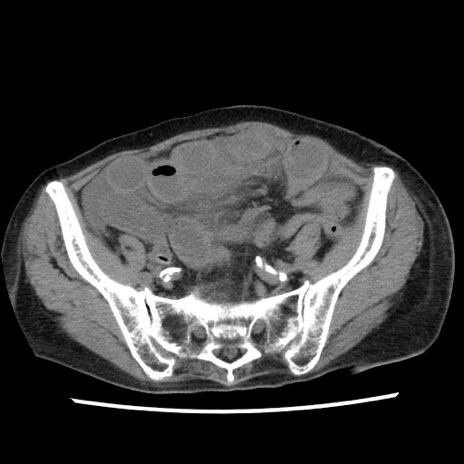

症例1(横断像)

【症例】80歳代女性

【主訴】腹痛

【現病歴】8時間前から腹痛あり来院。

【既往歴】糖尿病、脂質異常症、子宮体癌にて子宮全摘術

【身体所見】意識清明・会話良好だが腹痛で苦悶様、全腹部にわたって反跳痛と圧痛あり

【データ】WBC 13600、CRP 0.14、LDH 224、CK 90